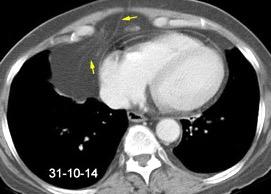

Linfoma de amigdala tratado diez años antes

Linfoma de Hodgkin..10

Linfoma no Hodgkin…2

Carcinoma.................... 7

Visualización en 21 casos

Positivo................6 (35%)

Dudoso.................3

Negativo..............8 (47%)

Vock. 1986.

(1 Burkitt-1 Indiferenciado)

Supradiafragmático......3 mama, pulmón, carcinoide tímico

Infradiafragmático........4

Ovario… ………………..3

Carcinomatosis peritoneal1